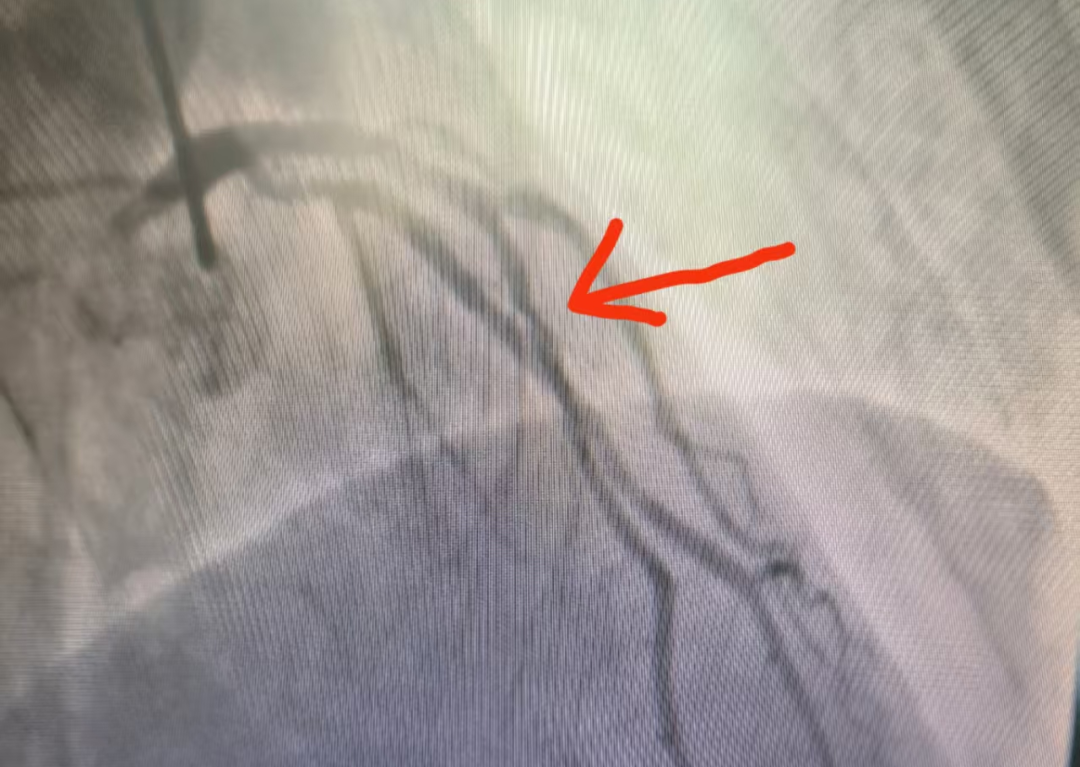

心血管疾病是威胁人类健康的“头号杀手”,葫芦岛市第二人民医院中医科王崇权主任团队在不断努力下,找到了新的破解之道。王崇权主任团队深谙“整体观念、辨证论治”的中医精髓,巧妙地将传统中医药智慧与现代医学技术相结合,在心血管危重症干预领域取得了令人瞩目的突破,为患者开辟了一条独具特色的康复之路。 神奇疗效,见证中医力量 心血管疾病作为慢性疾病,病情迁延,复发率较高,联合中医药的治疗,可以取得显著的效果。特别是在冠心病、心律失常、心衰、高血压、失眠、焦虑、便秘、痛症、体重管理等方面,尤为明显。 病例一:顽固性早搏患者经中药调理1个月,24小时动态心电图显示早搏次数从34061次降至153次,睡眠质量与精神状态同步改善。 5月10日数据 7月1日数据 病例二:47岁心梗后心衰患者,在西医规范治疗基础上配合中药汤剂,心脏射血分数(EF值)从34%提升至50%,胸闷、气短等症状明显改善。 5月16日数据 7月1日数据 病例三:58岁男性反复胸痛,冠脉造影显示前降支中段重度狭窄(70%),经三个月中药治疗后复查冠脉CT,狭窄程度减轻为轻度(30%)。 治疗前造影 治疗后诊断结果 病例四:46岁男性,反复胸痛伴焦虑状态,汤药治疗后胸痛明显缓解,复查冠脉较前明显改善。 治疗前 治疗后 这四个典型病例充分展示了中医药在心血管疾病防治中的独特优势。这种源于传统医学的整体调理理念,不仅针对病症本身进行治疗,更注重恢复机体的阴阳平衡,激发自身的修复能力,为心血管疾病患者提供了特色鲜明的治疗选择。 葫芦岛市第二人民医院中医科在王崇权主任的带领下,持续深入挖掘中医药宝库,致力于在心血管疾病防治领域开展更多的临床实践与研究,为提升人类健康水平贡献中医智慧。 中医科简介 葫芦岛市第二人民医院中医科集中医预防、治疗、康复、保健于一体,以深厚的中医药文化为底蕴,秉承“整体观念,辨证论治”的核心思想,运用传统中医理论和方法,结合现代医学技术,为患者提供优质中医诊疗服务。 运用中药饮片、颗粒、膏方、针灸、推拿、拔罐、中药外敷、刮痧、穴位贴敷、耳穴压豆等多种方法辨证施治,针对不同病症的病因病机,精准调节脏腑功能,实现内外兼治,标本兼顾。 1、内科疾病调治 高血压、冠心病(心绞痛)、心律失常、PCI术后康复、慢性疼痛、顽固性失眠、头痛眩晕、疲劳综合征及免疫力调节等。 2、亚健康状态干预 基于中医体质辨识(气虚/阳虚/阴虚/痰湿/湿热等),针对性调理慢性疲劳、睡眠障碍、焦虑状态及体质偏颇。 3、肿瘤辅助疗法 缓解放化疗副作用(消化道反应、骨髓抑制、癌因性疲乏),协同增强免疫功能,改善生存质量。 4、精准体重管理 融合体质辨证(BMI/体脂分析)、中药内调(代茶饮/膏方)、外治疗法(针灸/穴位埋线/雷火灸)及个性化运动膳食指导,构建科学减重体系。 人民医院 人民名医 王崇权 副主任中医师 硕士研究生 ·葫芦岛第二人民医院心脏中心门急诊主任、中医科主任 ·国家中医药管理局龙砂医学流派五运六气第四批传承人 ·全国医药技术市场协会心衰防治专业委员会委员 ·中国医药信息学理事会心力衰竭学术委员会委员 ·中国民族医药学会委员 ·辽宁省中西医介入委员会常务委员 ·葫芦岛医学会心血管病分会委员 ·葫芦岛医学会心电生理与起搏学会分会委员 ·葫芦岛市医学会急诊医学分会委员 专业特色:师从辽宁中医药大学附属医院知名专家张明雪教授,从事临床工作10余年,擅长胸痹、心悸、喘证、失眠等疾病的中医传统汤药治疗;中西医结合治疗冠心病、心力衰竭、高血压、心律失常等心血管疾病;心血管疾病危重患者的抢救及急诊PCI治疗等。在涌泉贴、耳穴压豆、穴位按摩、中药足浴治疗失眠等内科疾病方面效果显著。开设中医减肥门诊,中西医结合进行系统体重管理。顺利完成急性心肌梗死溶栓治疗百余例,冠状动脉造影及PCI手术2000余例,成功抢救危重患者数百例。 学术成就:多次前往北部战区总医院、辽宁中医药大学附属医院、大连市友谊医院等知名医院进修学习,在中西医结合治疗心血管疾病领域有所突破。参与编撰书籍《从温病论治病毒性心肌炎》《 基于网络药理学探讨肺癌培元固本法的用药规律研究》《医养结合概论》,发表《血府逐瘀汤联合他汀治疗高脂血症疗效分析》《归脾汤加减结合降压药治疗老年性高血压临床效果观察》等多篇文章。参与课题《评价祛痰化瘀、益气温阳法治疗冠心病合并缓慢性心律失常的临床研究》《基于真实世界的冠心宁片治疗稳定性冠心病的多中心病例注册登记研究》的临床研究及病例收集分析。主持葫芦岛市课题《中医联合外治法通过调控RASS系统干预肾阳不足型高血压研究》。 出诊时间: 🔸健康体重管理门诊:每周一上午(门诊三楼4号诊室) 🔸心内中西医科:每周二上午(心脏门急诊4诊室) 顾平 主治医师 中医内科学硕士 ·葫芦岛市第二人民医院中医科主治医师 ·辽宁省中医药学会针刀分会委员 ·江苏省研究型医院学会睡眠分会委员 ·江苏省中医药学会针灸分会委员 专业特色:曾于中国中医科学院西苑医院进修心血管疾病相关的中医治疗。擅长中医辨证方药治疗冠心病、心力衰竭、高血压、焦虑证、抑郁证;针药结合治疗失眠症、脾胃病;针灸治疗颈肩腰腿痛;针灸美容及代谢综合征的体重管理。先后发表5篇核心期刊论文。主持课题“加味二仙汤治疗阴虚阳亢型高血压病的血浆代谢组学研究”一项。参与编著《中医药治疗病毒性心肌炎》和《冠心病证候研究》两部著作。